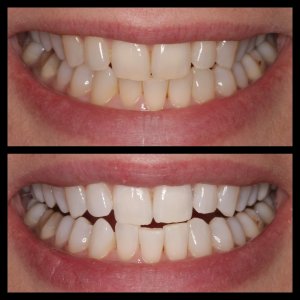

ΛΕΥΚΑΝΣΗ ΔΟΝΤΙΩΝ